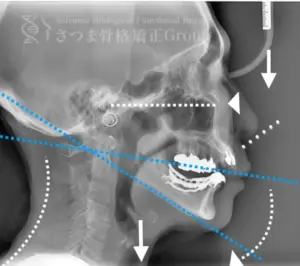

30代男性 S様 初回効果

下顎に強い後方回転あり 中顔面が伸びて下方に落ちる。 中顔面の奥行きを失っている。 下顎の後方回転により上部頚椎C1、C2の可動域が狭い→椎骨動脈への刺激により交感神経が優位。

Mild jaw deformity present. Posterior rotation of the mandible. The midface is elongated and has dropped downward. Loss of depth in the midface. Cervical spine straightening (straight neck).

AFTER

咬筋をリリースし、下顎の牽引法により顎の前方回転位に誘導 中顔面の奥行きを作り、左右差を整顔し中顔面を短縮させ頚椎の前弯角を強化。

Release the masseter and upper cervical spine to achieve forward rotation of the jaw.

Using the Satsuma method, create depth in the midface and shorten it.

Enhance the cervical lordosis angle.